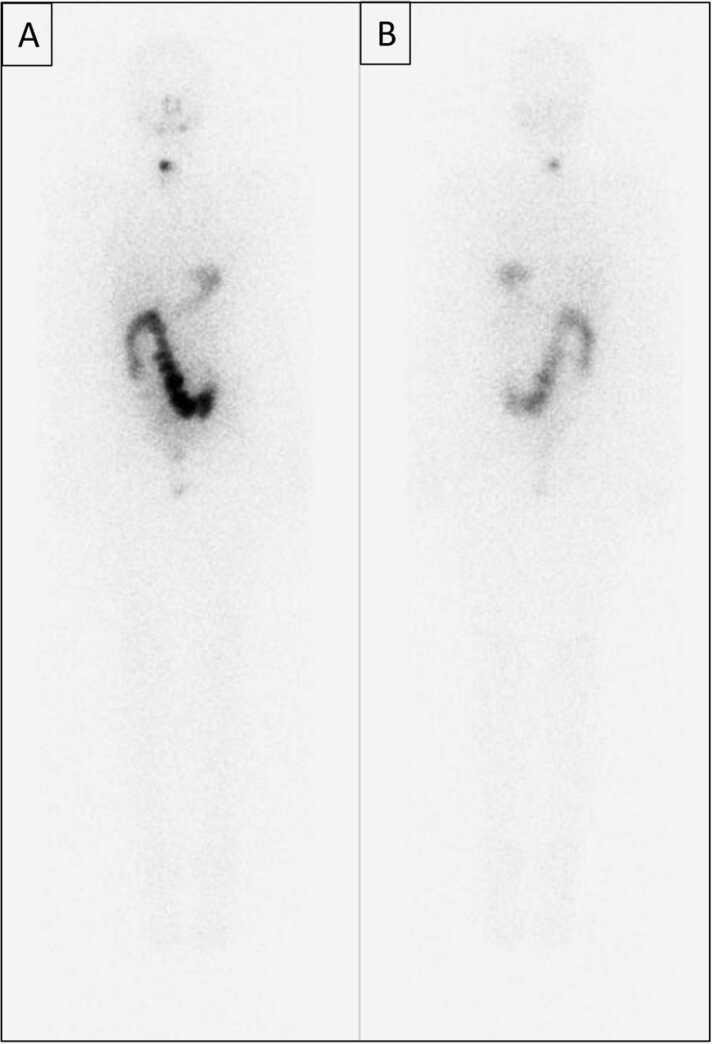

As new molecular tracers are identified to target specific receptors, tissue, and tumor types, opportunities arise for the development of both diagnostic tracers and their therapeutic counterparts, termed "theranostics." While diagnostic tracers utilize positron emitters or gamma-emitting radionuclides, their theranostic counterparts are typically bound to beta and alpha emitters, which can deliver specific and localized radiation to targets with minimal collateral damage to uninvolved surrounding structures. This is an exciting time in molecular imaging and therapy and a step towards personalized and precise medicine in which patients who were either without treatment options or not candidates for other therapies now have expanded options, with tangible data showing improved outcomes. This manuscript explores the current state of theranostics, providing background, treatment specifics, and toxicities, and discusses future potential trends.

随着新的分子示踪剂被确定用于靶向特定受体、组织和肿瘤类型,开发诊断示踪剂及其治疗对应物(即“治疗诊断剂”)的机会应运而生。诊断示踪剂利用正电子发射体或γ发射放射性核素,而它们的治疗诊断对应物通常与β和α发射体结合,这可以将特定的局部辐射传递到靶点,同时对未受影响的周围结构造成最小的附带损伤。这是分子成像和治疗领域令人兴奋的时期,也是迈向个性化精准医学的一步,在这种医学模式下,那些原本没有治疗选择或不适合其他疗法的患者现在有了更多选择,切实的数据表明治疗效果有所改善。本文探讨了治疗诊断学的现状,提供了背景、治疗细节和毒性,并讨论了未来的潜在趋势。